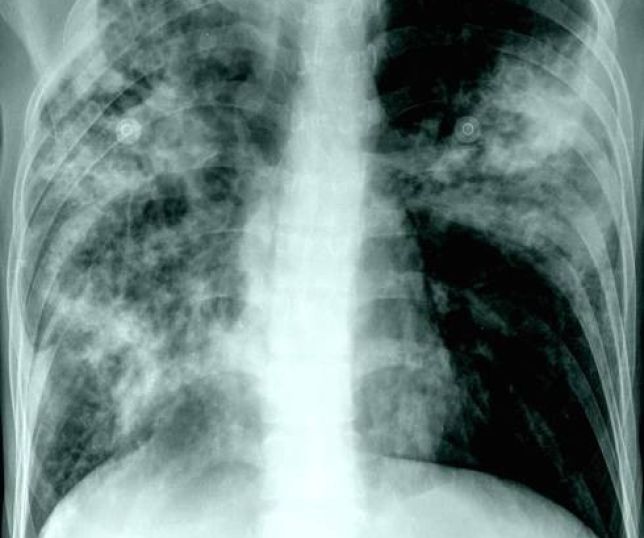

O apresentador Silvio Santos morreu na madrugada deste sábado, aos 93 anos, em São Paulo, em razão de uma broncopneumonia

O apresentador Silvio Santos, um dos maiores nomes da história da TV brasileira, morreu aos 93 anos, na madrugada deste sábado (17/8). Conforme boletim médico divulgado pelo Hospital Albert Einstein, a causa da morte do apresentador foi uma broncopneumonia após infecção por influenza.